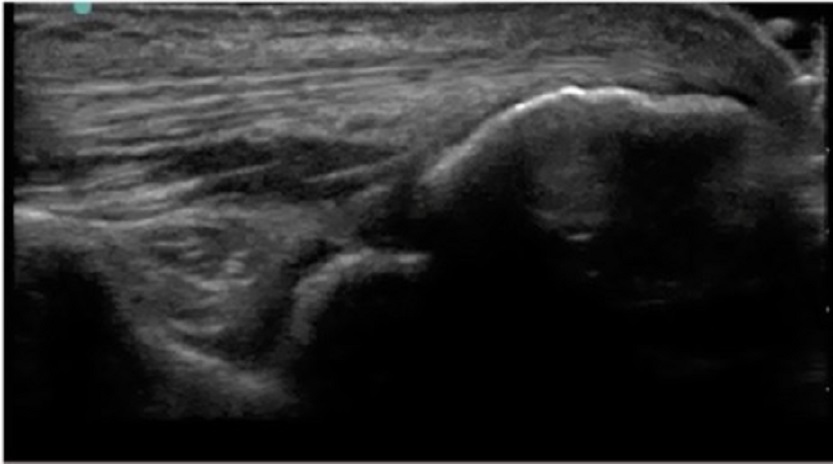

肘部关节内注射后陷窝图像